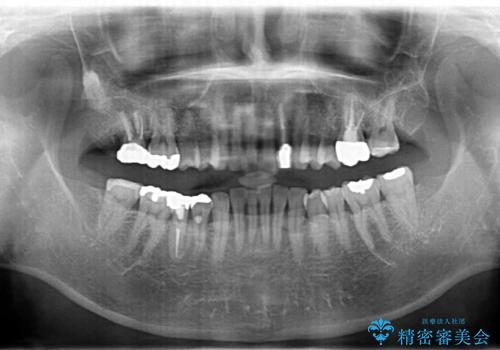

治療後、明るくなった口腔内を見て大変満足いただくことができました。

色調だけでなく、精密な治療を行うことで虫歯の再発の確率を下げることも可能になります。